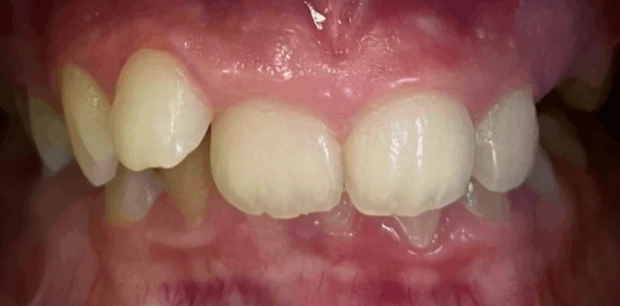

Ортодонтия

Ортодонтическое лечение элайнерами

Пациентка А., 43 года обратилась с жалобами на эстетичесую неудовлетворенность внешним видом улыбки из-за скученности зубов. Проведено ортодонтическое лечение элайнерами. Лечение проводилось 1,5 года.